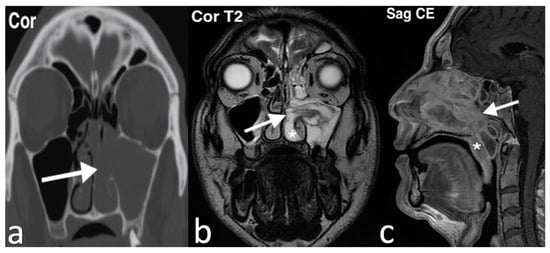

3.2.8. Antrochoanal Polyp